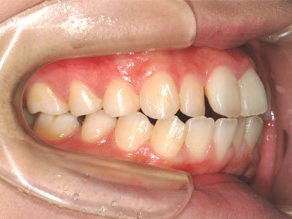

上顎の劣成長 (成長不足) による反対咬合で、上顎は拡大装置と上顎前方牽引装置を併用し前方方向への成長を促して前歯の咬み合わせを改善した後に、上下顎の前歯をマルチブラケット装置で並べました。治療の期間は2年でした。

1期治療終了時